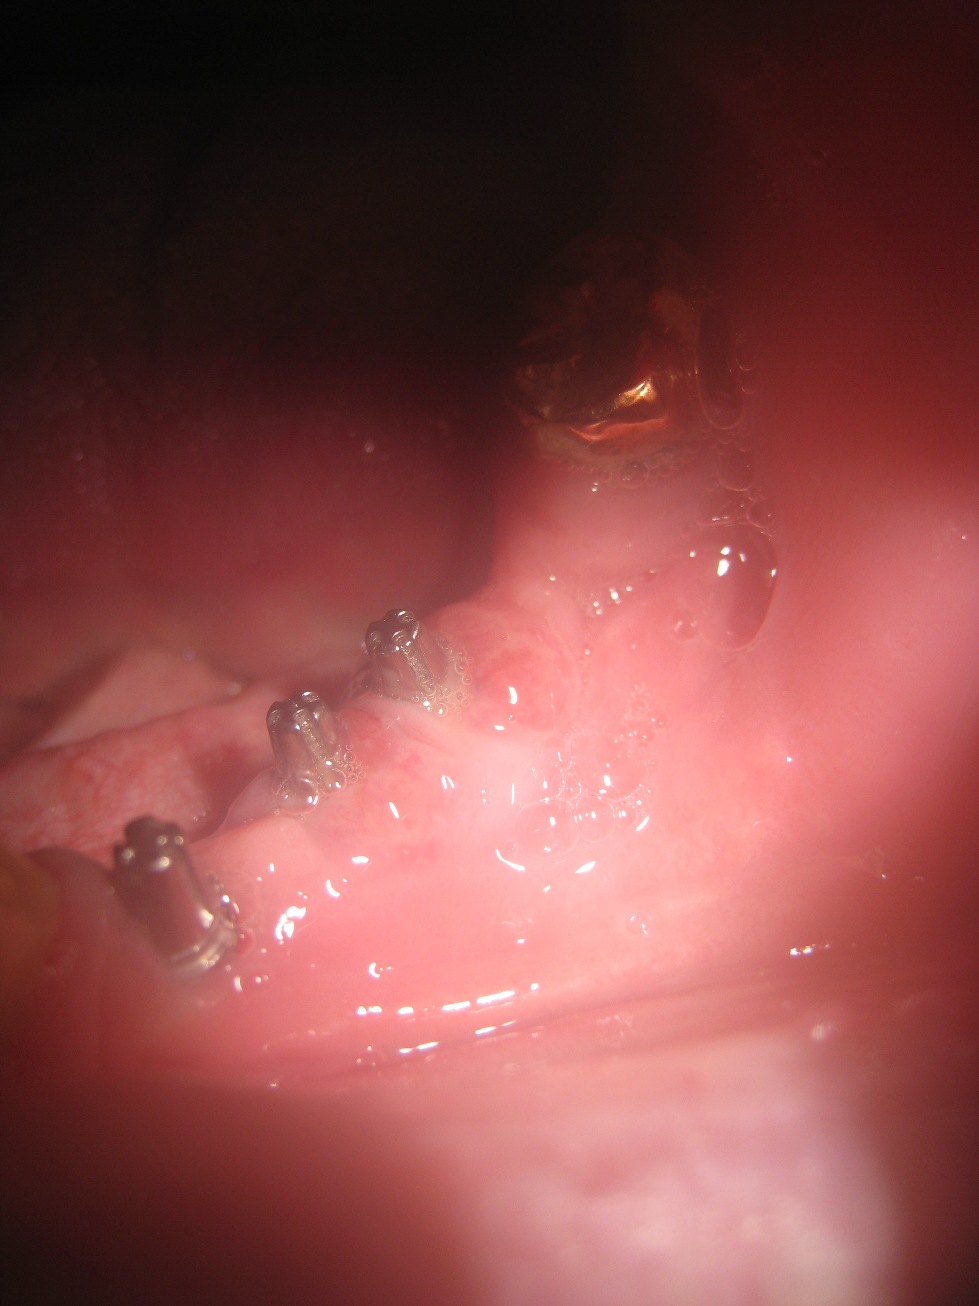

Extraction de l’implant trinon par O C

j’ai fait posé 3 implants de marque (implant Monobloc Biomédical trinon) origine Allemagne? chez le dentiste qui travaille avec endurance Implant, j’ai perdu un premier implant 2 mois après la pose, j’ai fait une péri-implantite dentaire, avec poche de pus (grave), j’ai joint par téléphone le cabine dentaire près de Barcelone, aucun problème au dire du dentiste d’après ma radio ? Pourtant le médecin stomatologue ma recommande d’urgence de revoir le dentiste pour faire coupé l’implant qui été sortie de l’os? risque d’infection de la mâchoire, car mal posé d’après lui. je vient encore d’avoir de nouveau des problèmes sur un 2eme implants infection a la base, je vient de faire une radio l’implant est sortie de l’os?